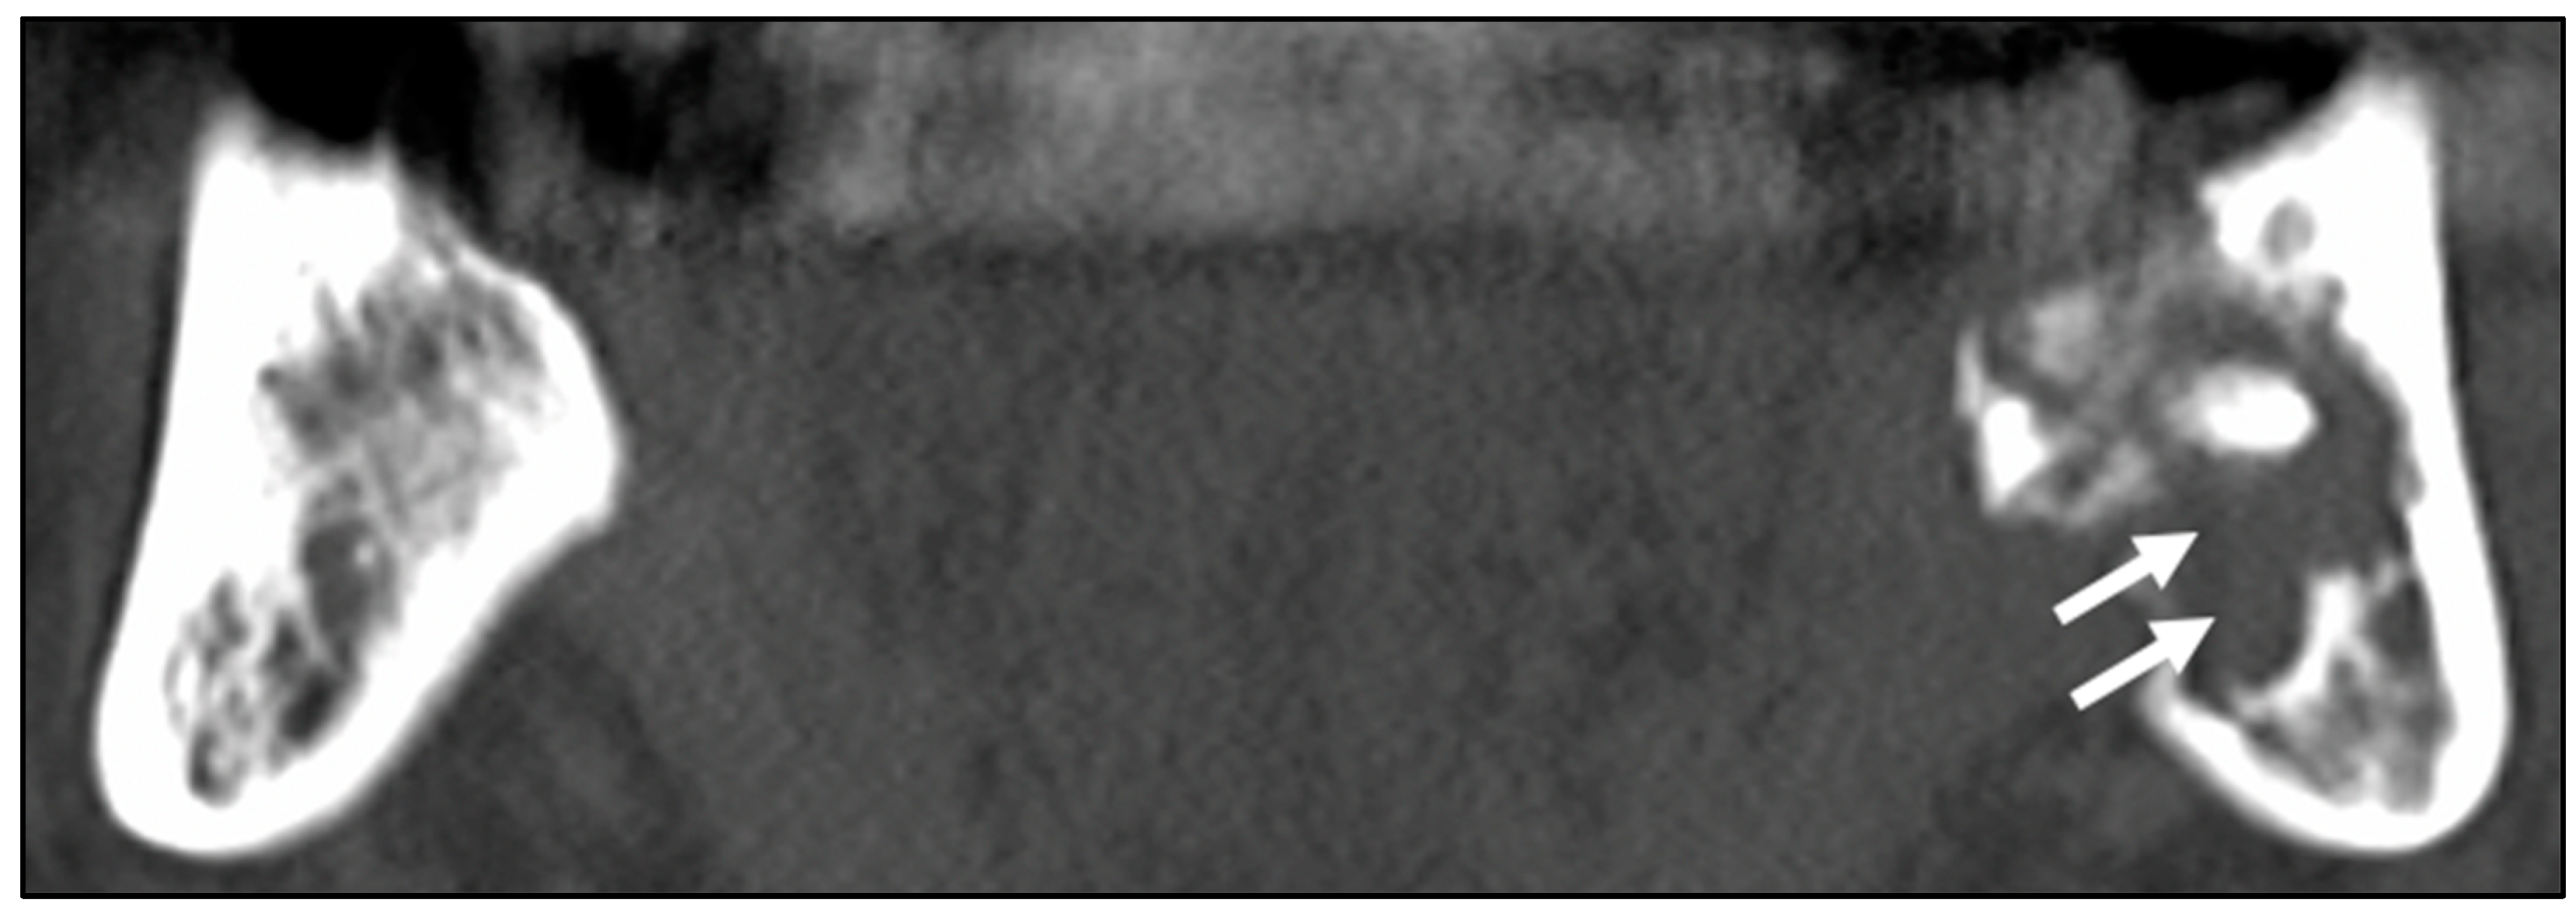

3.1. Patients’ Clinical Characteristics and CT Image Findings

- Miyamoto, I.; Tanaka, R.; Kogi, S.; Yamaya, G.; Kawai, T.; Ohashi, Y.; Takahashi, N.; Izumisawa, M.; Yamada, H. Clinical Diagnostic Imaging Study of Osteoradionecrosis of the Jaw: A Retrospective Study. J. Clin. Med. 2021, 10, 4704. [Google Scholar] [CrossRef]

- Obinata, K.; Shirai, S.; Ito, H.; Nakamura, M.; Carrozzo, M.; Macleod, I.; Carr, A.; Yamazaki, Y.; Tei, K. Image findings of bisphosphonate related osteonecrosis of jaws comparing with osteoradionecrosis. Dentomaxillofacial Radiol. 2017, 46, 20160281. [Google Scholar] [CrossRef]